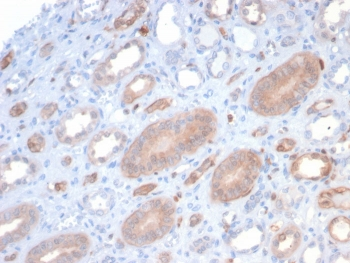

Cathepsin D Antibody

| Description | Cathepsin D Antibody |

| Tested applications | FC, ICC, IHC, IP, WB |

| Reactivity | Human, Mouse |